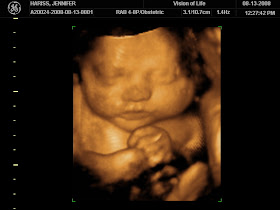

I had my ultrasound at around noon today and baby measured around 36/37 weeks and they estimate his weight to be about 6 pounds! Dr. Keith said he is in the 70% percentile but still not too big to be a concern to me just yet. Whew!! Unfortunately, he is so big and his head is so low that we were unable to get a good picture of him, but I did see his big round belly and little beating heart.